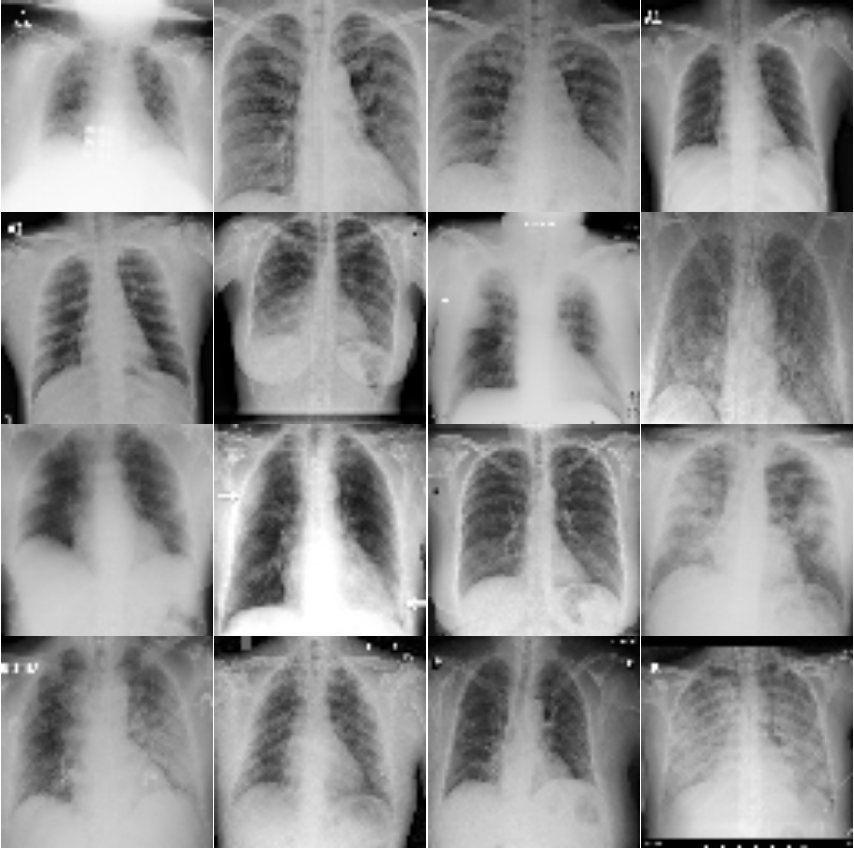

| Panel A | Panel B |

|---|---|

|

|

From observation of Figure 4, it is visible for humans that the chest areas are clear in the healthy chest X-ray images. However, the images for COVID cases are not quite clear. This is an indication that there are inflammatory cells or other related body fluids filled in the chests. Instead of air which shows up on the pictures to be clear area, these areas in COVID cases tend to be cloudy and unclear.

This section presents visualization of the proposed architecture. These visualizations are presented in Figure 5. Unlike Figure 2 that is an executive summary with each position representing many samples, these visualizations in Figure 5 are sample-wise plots. In other words, the 10 original images that are sized 128 by 128 in Panel A and Panel B are the same samples in the second row, 1st Conv. Layer, and the third row, 2nd Conv. Layer.

Visualization Interpretation The plot in Figure 5 of the original images for COVID-19 patients has grey and cloudy textures in chest area. Because an X-ray picture is at its brightest when most of the light beams emitted are bounced back from the object, we can observe bones to be the color “white” while the margin to be completely “black”. For muscle and organs inside human body, X-ray beams that are emitted can only partially be collected and this causes the greyscale on the X-ray images in chest area. For COVID-19 patients, there are grey and shaded area in the chest X-ray pictures. This is due to the inflammatory fluid when patients exhibit pneumonia-like symptoms. The fluid inside chest area is a consequence of human immune system fighting against outside diseases. This shaded (as seen in Panel A of Figure 5) prevents us from observing the clear location of lungs. This is different in Panel B where the lung areas are dark and almost black, because a healthy lung is filled with air (i.e. normal cases and X-ray image presents color black). The black and white contrast in the two panels is directly related to how much inflammatory fluid there is in human lungs. This contrast translates to greyscale on pictures and it is directly related with COVID cases and non-COVID cases (i.e. response variable ). The same contrast can be seen using the new variables (these are ’s based on equation 4) in the 1st Conv. Layer (sized 61 by 61). For COVID-19 patients, the lung area is cloudy and unclear while the healthy cases it is clearly visible. This is not a surprising coincidence because the proposed new variable modules, ’s, are engineered using equation 4 which relies on the response variable in training set. The images sized 61 by 61 from the proposed algorithm is a direct translation of not only the original pixels but also response variable. In other words, this visualization presents how I-score sees image data.

| Panel A: | Panel B | |

| True Label: COVID | True Label: Non-COVID | |

| Input Images: 128 by 128 | Input Images: 128 by 128 | |

| (Randomly select 10 samples) | (Randomly select 10 samples) | |

| Row (a) |  |

|

Discussion for Figure 5.

This figure presents visualization summary for 10 randomly sampled images from COVID class and non-COVID class (each has 10). Panel A is for COVID patients and Panel B is non-COVID people. The first row plots the original images that are sized 128 by 128. The 1st Conv. Layer generates new variables. We plot the same 10 images from both classes using these 3,721 variables in the second row. We also print the predicted COVID probabilities on top left corner of each image. The 2nd Conv. Layer generate variables. We plot the same 10 image samples from both classes using these 900 variables in the third row. We also print the predicted COVID probabilities on top left corner of each image assuming using only these 900 variables as predictors. The plot of the original images for COVID-19 patients has grey and cloudy textures in chest area. This is due to inflammatory fluid when patients exhibit pneumonia-like symptoms. This shaded (as seen in Panel A) prevents us from observing the clear location of lungs. This is different in Panel B where the lung areas are dark and almost black which means the lung is filled with air (i.e. normal cases). The black white contrast in the two panels is directly related to how much inflammatory fluid there is in human lungs which translate to greyscale on pictures. The same contrast can be seen using the new variables (these are ’s based on equation 4) in the 1st Conv. Layer (sized 61 by 61). For COVID-19 patients, the lung area is cloudy and unclear while the healthy cases it is clearly visible.

|

Discussion for Figure 5.

Original Images to 1st Conv. Layer. The input images are sized 128 by 128. With the 1st Conv. Layer constructed, we have new variables. We trace back to the same samples as shown in the first row of Figure 5 and use these 3,721 variables only. When we plot these samples with these new variables, we resize them back in matrix form of 61 by 61. Panel A is for COVID class and Panel B is for non-COVID class. In addition, we use Model 1 in Table 4 to produce the texts that states predicted probability of COVID class. The red color implies ground truth to be COVID class (Panel A) and the green color implies ground truth to be non-COVID class (Panel B).

1st Conv. Layer. to 2nd Conv. Layer. From the resulting matrix of the 1st Conv. Layer, we are left with 3,721 variables. We go through the proposed design in Table 4 and we create a new convolutional layer, i.e. 2nd Conv. Layer. This new layer has variables. We take the same 10 sampled images from before and we use these 900 variables to present these images. In this presentation, we resize these 900 variables into shape 30 by 30. In other words, we get a smaller matrix that we can plot that exhibit mini version of similar patterns as before. We use Model 4 to generated the predicted probabilities. These probabilities are printed on the top left corner of each image and they are color coded similarly as before (red probabilities have ground truth of COVID class while green probabilities have ground truth of non-COVID class).